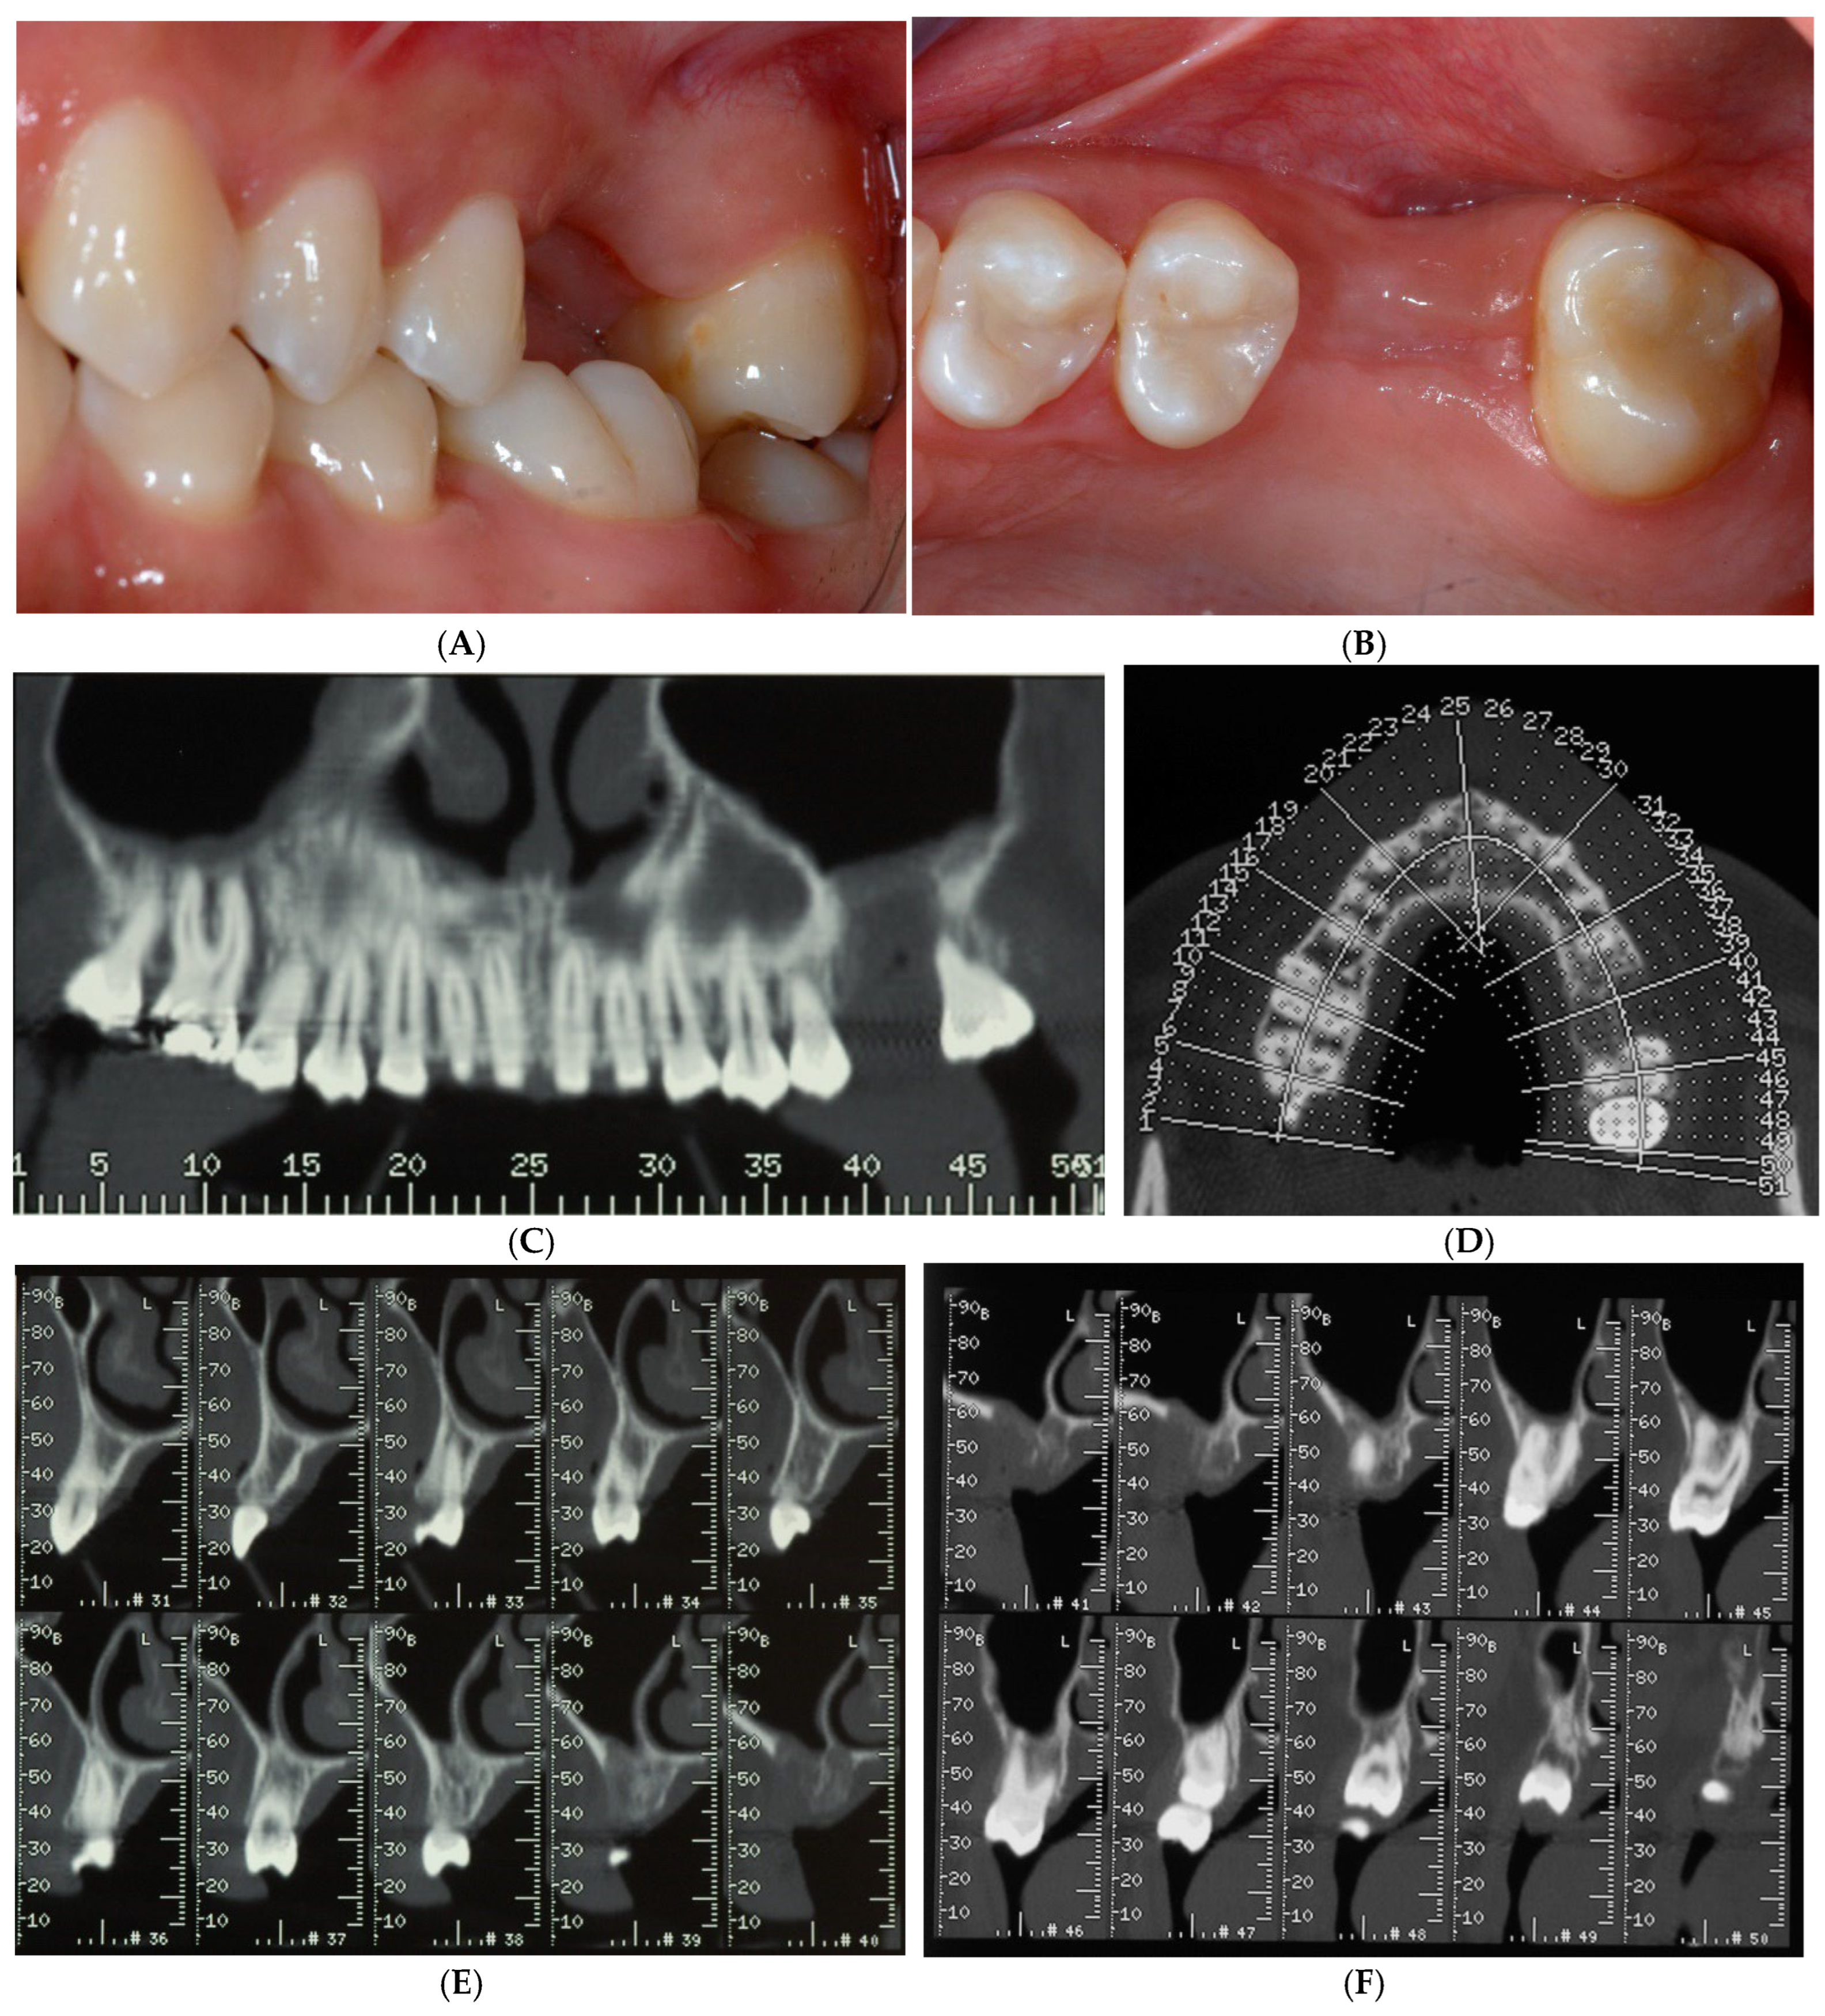

After making the crestal incision, two vertical buccal releasing incisions—mesial to the second premolar and distal to the second molar—were performed. Then, a mucoperiosteal flap was raised, revealing the wide ridge deficiency (approximately 5, 7, and 9 mm in the mesio-distal, bucco-palatal, and corono-apical directions, respectively), highlighting the impossibility of achieving proper implant stability (Figure 3A,B). Then, a copious bleeding recipient site was created by bur perforations through the medullary spaces. A TR-dPTFE membrane (Cytoplast® Ti 250 Buccal, Osteogenics Biomedical, Lubbock, TX, USA) was shaped and trimmed with scissors to fit the ridge defect (Figure 4A), taking care to position the membrane edges 1.5 mm away from the adjacent roots, and stabilized with two pins on the buccal side. A graft of 100% NH embedded in a silica gel matrix (NanoBone® Artoss, Rostock, Germany), in the form of 0.6 × 2 mm granules, wetted with sterile saline (Figure 4B), was applied and compacted with a spoon/plugger tool to avoid leaving voids, but without over-compacting the material (Figure 4C). The membrane was moved to the palatal side and stabilized with an additional pin to the palatal bone wall (Figure 4D,E). A continuous periosteal incision along the entire length allowed the buccal flap to move coronally, followed by tension-free suturing using horizontal mattress and single stitches (Figure 5A) with PTFE material (Cytoplast® suture, Osteogenics Biomedical, Lubbock, TX, USA), which were removed 14 days later (Figure 5B). Healing was uneventful, and after a period of 10 months (Figure 6A–C), the site was re-opened for membrane removal and implant insertion. A smaller paramarginal trapezoidal mucoperiosteal flap, sparing the periodontum of the adjacent teeth, was raised (Figure 6D,E). The membrane was easily removed, and the defect appeared to be completely regenerated (Figure 6F). A 4 mm wide trephine bur (Stoma®, Emmingen-Liptingen, Germany) was used to harvest a bone biopsy (Figure 7A), measuring 3 mm in diameter and about 6 mm in length (Figure 7B), so as not to extend the future implant bed preparation. The implant bed was then definitively prepared with the drill dedicated to the chosen implant (Figure 7C), a 5.0 × 9 mm implant (Camlog® Screw Line Promote Plus Biotechnologies, Basel, Suisse). The bone biopsy was immediately fixed in 10% neutral buffered formalin and stored at room temperature. The specimen was then decalcified in formic acid, dehydrated in progressively more concentrated ethanol, and finally embedded in paraffin. Sections of 5–6 µm thickness were cut with a microtome (Leica SM 2.400, Solms, Germany) and stained with hematoxylin and eosin and the Azan–Mallory staining technique for light microscopy. Histological evaluation and photo documentation were performed using the Axiophot microscope (Zeiss, Göttingen, Germany) at 12.5×, 25×, 100×, 200×, 400× magnifications.

After buccal flap reflection with two vertical releasing incisions, wide horizontal bone defect was evident (A,B).

Titanium-reinforced dense polytetrafluoroethylene (TR-dPTFE) membrane was shaped and trimmed with scissors to fit ridge defect (A) and stabilized with 2 pins on buccal side. Particulate graft of 100% nanocrystalline hydroxyapatite (NH) embedded in a silica gel matrix, wetted with sterile saline (B), was packed to fill defect (C). Membrane was moved to the palatal side and stabilized with additional pin to palatal bone wall (D,E).